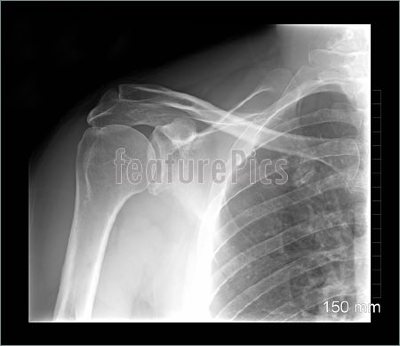

Its supposed to look like this...

Shoulder-Xray-752382.jpg